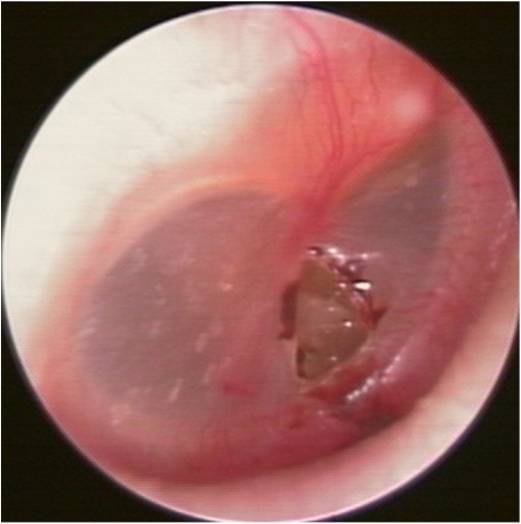

・そのため、当科ではなるべく早く応急処置を行い、人工鼓膜で穴をふさぎます。

・90%は外来での保存的な治療で1ヶ月以内に穿孔が閉鎖しますが、穴が大きなもの、もともと鼓膜が薄いもの、感染を起こして中耳炎を併発したものでは穴が閉じません。

・その場合は鼓膜形成術(接着法)と言って、外耳道経由で自分の皮下組織を鼓膜穿孔部に自家移植して穴をふさぐ手術をします。日帰りまたは1泊の手術で対応が可能です。